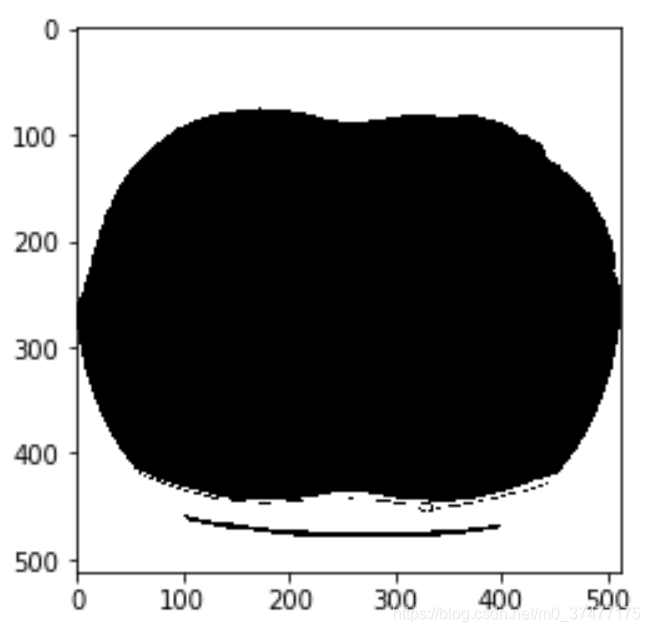

显示阈值分割之后的图像:

2. 种子生成法填充空气

#利用种子生成算法,填充空气

ConnectedThresholdImageFilter = sitk.ConnectedThresholdImageFilter()

ConnectedThresholdImageFilter.SetLower(0)

ConnectedThresholdImageFilter.SetUpper(0)

ConnectedThresholdImageFilter.SetSeedList([(0,0,0),(size[0]-1,size[1]-1,0)])

#得到body的mask,此时body部分是0,所以反转一下

bodymask = ConnectedThresholdImageFilter.Execute(threshold)

显示结果:

像素反转:

bodymask = sitk.ShiftScale(bodymask,-1,-1)